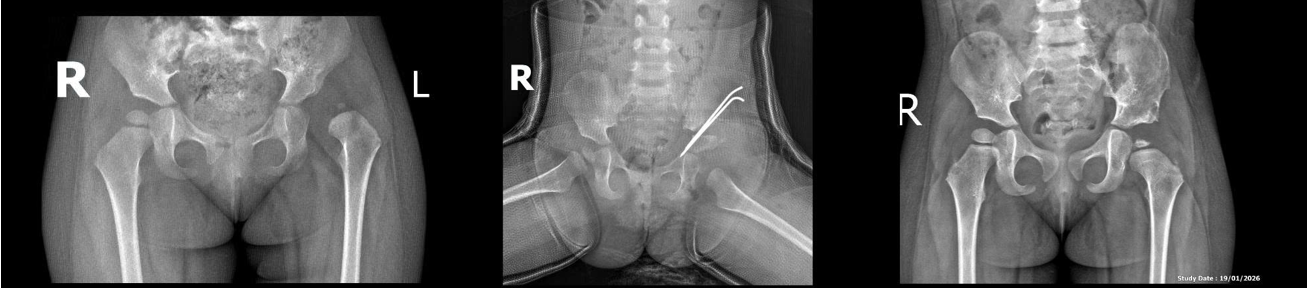

Hình ảnh Xquang bệnh nhân nữ 7 tuổi, trật khớp háng P, trước và sau mổ.

Hình ảnh Xquang bệnh nhân nữ 32 tháng, trật khớp háng T, trước và sau mổ